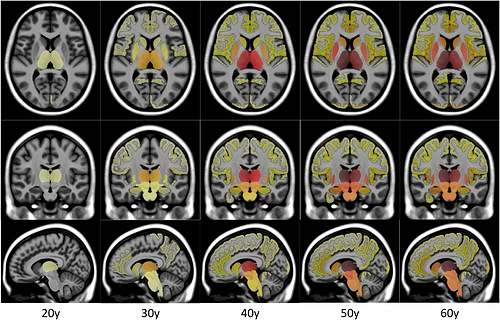

Une IA décèle les premiers signes de la sclérose en plaques

Ces résultats soulignent l’importance prise par l’intelligence artificielle…